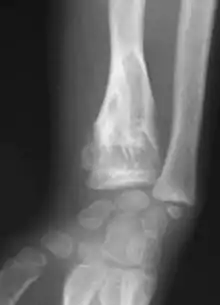

X-ray showing enchondromas localized in the humerus of a 37-year-old patient affected with Ollier disease

Enchondromas localized in the upper part of the humerus of the same patient